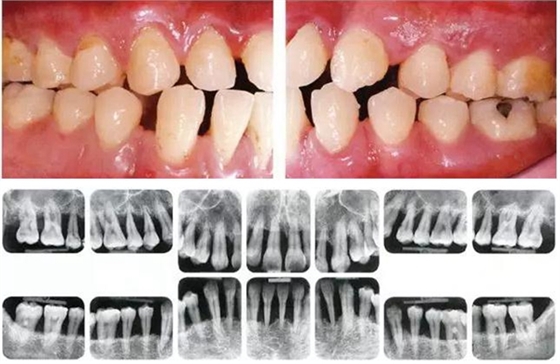

●33歲男性 侵襲性牙周炎廣泛型口腔內(nèi)照片

33歲男性,吸煙(1天10根,12年吸煙史)。菌斑控制狀況不好,牙周探診全頜牙周袋深5~10mm之外,全頜性牙周袋出血,部分牙周袋有排膿現(xiàn)象。X片可觀察到全頜性重度骨吸收。通過(guò)以上檢查可診斷出該患者為侵襲性牙周炎廣泛型。視診可知牙齦雖然有炎癥,但沒(méi)有出現(xiàn)嚴(yán)重浮腫,沒(méi)有大量牙結(jié)石沉積。